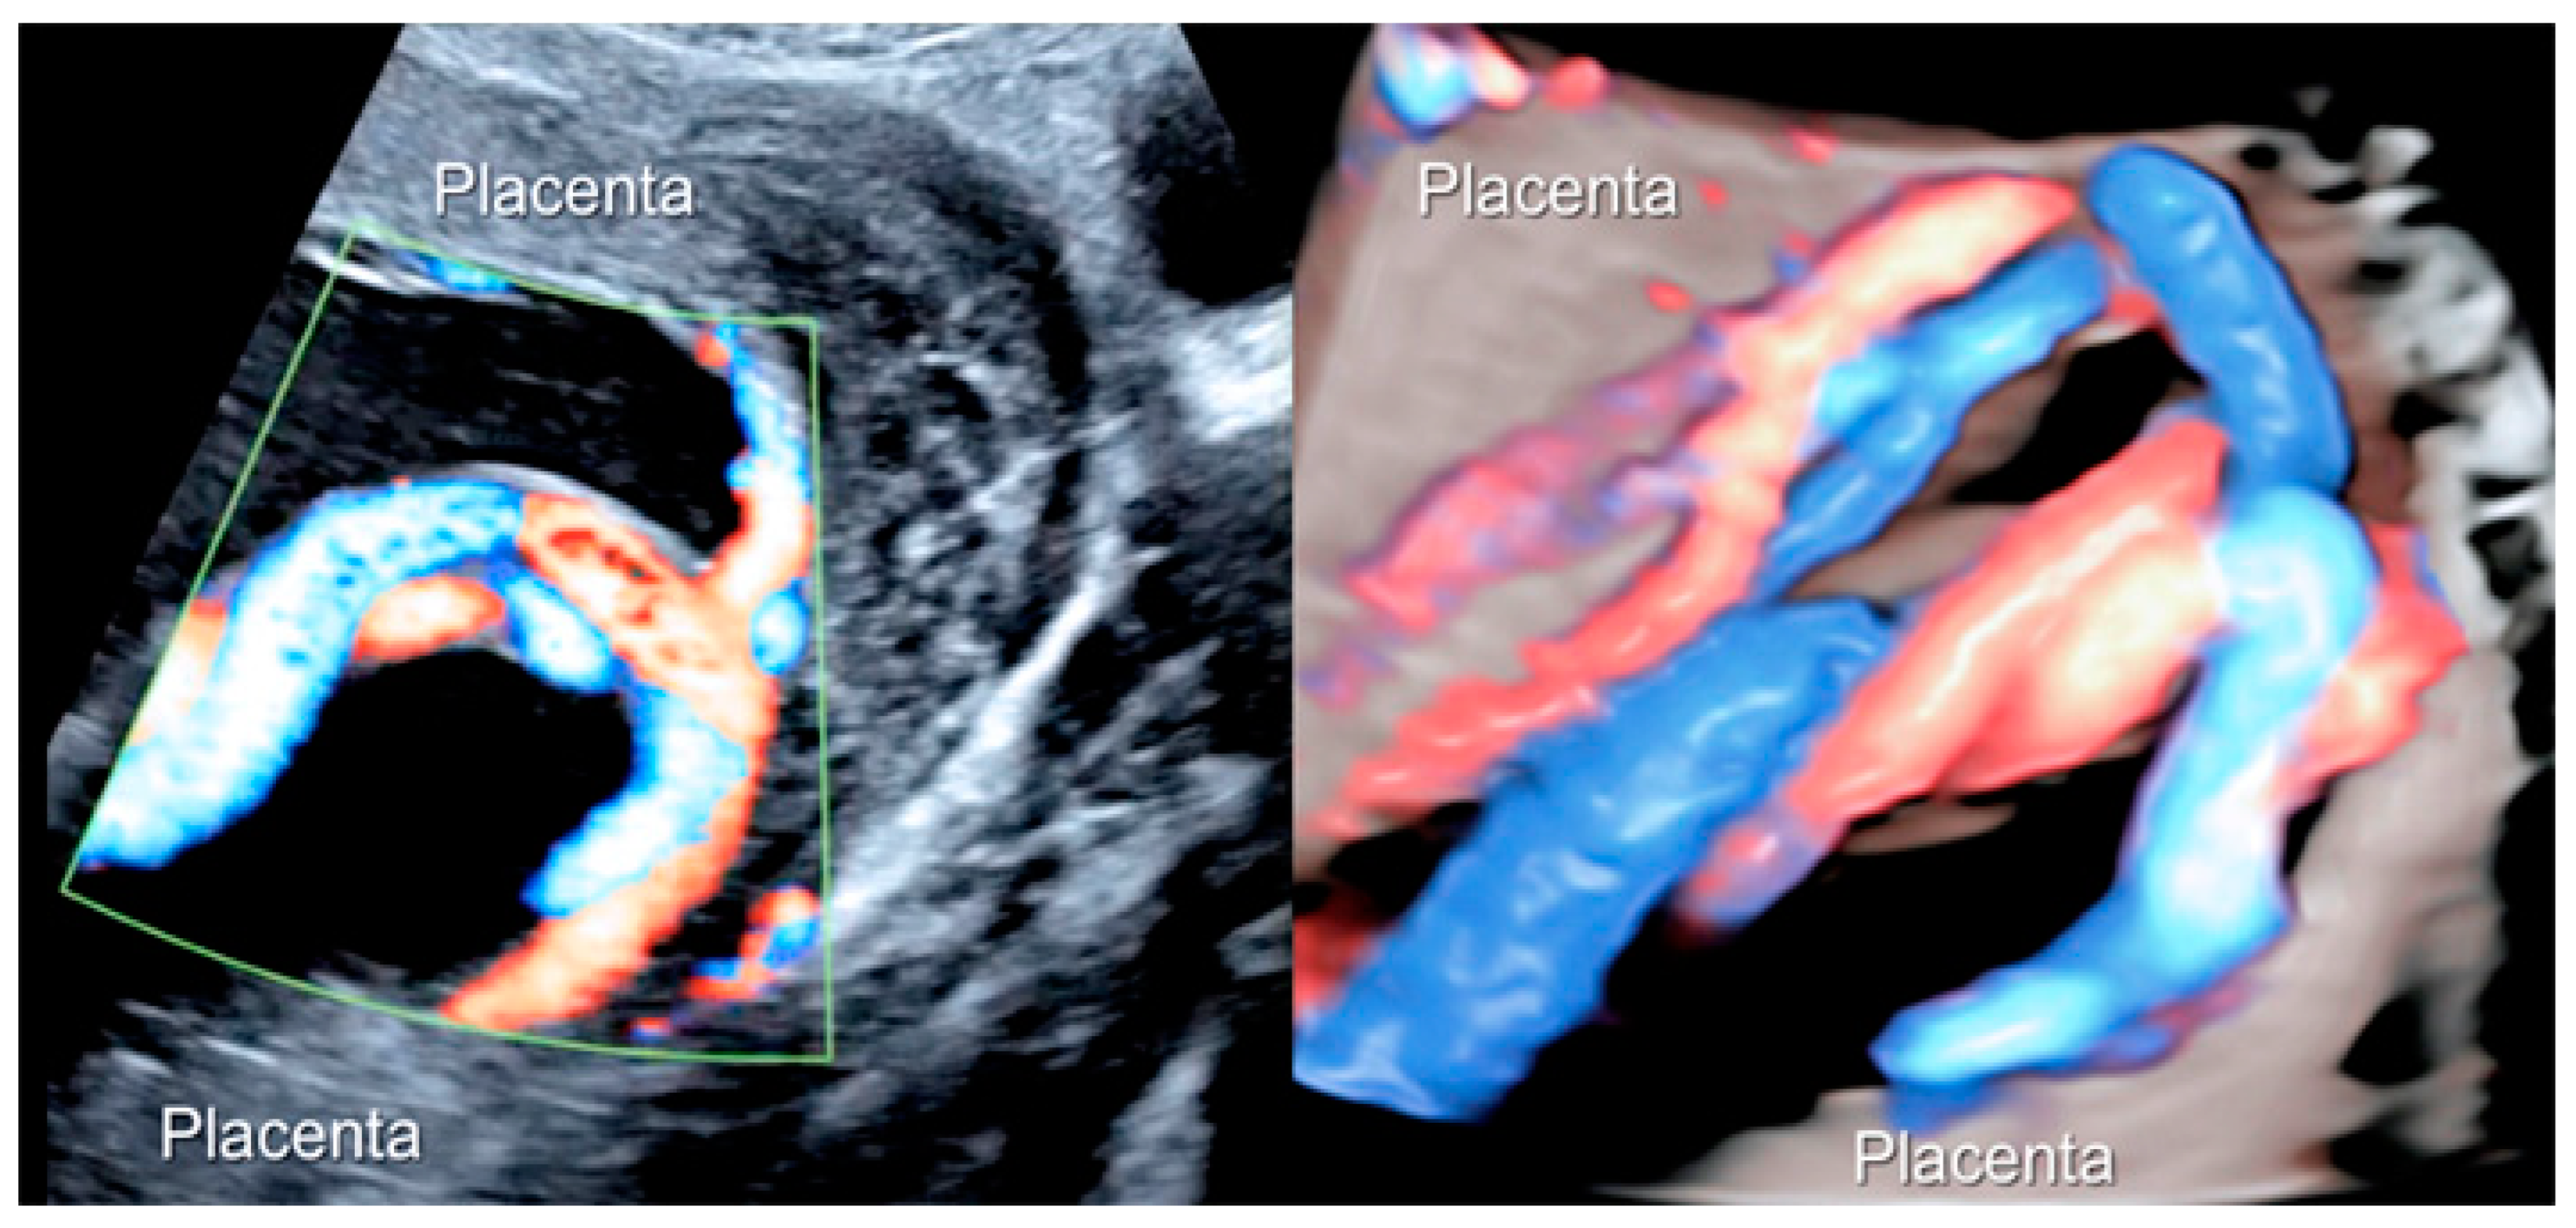

3.1.3. Bilobed Placenta and Succenturiate Lobe

Figure 5.

Two-dimensional color Doppler ultrasound and three-dimensional ultrasound using HD-Live™ flow showing a bilobed placenta. When an accessory lobe is detected (succenturiate) in the lower part of the uterus, careful evaluation with ultrasound for vasa praevia and velamentous cord insertion should be performed.